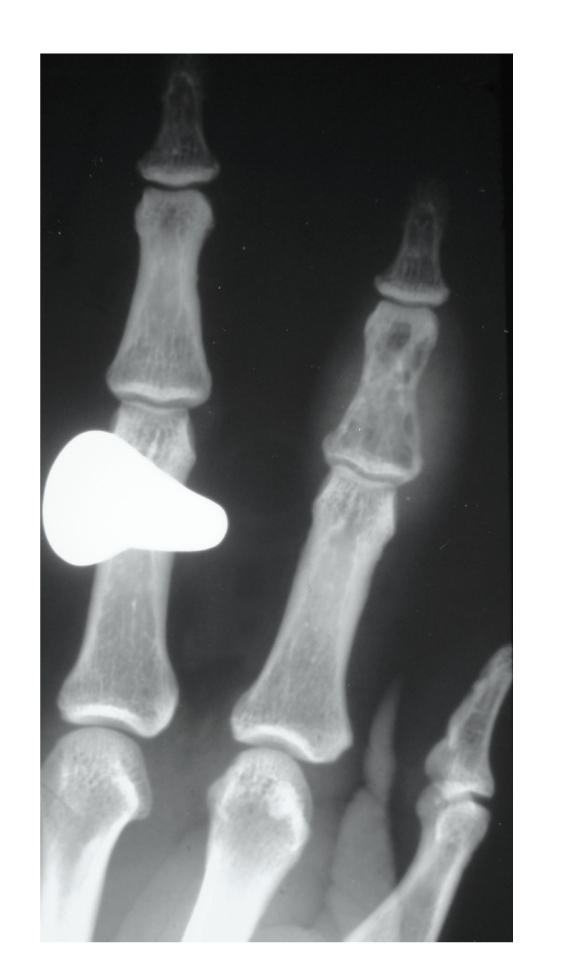

Sickle cell anaemia is an autosomal recessive genetic condition producing abnormal haemoglobin HbS molecules that result in stiff and sticky red blood cells leading to unpredictable episodes of microvascular occlusions. The clinical and radiological manifestations of sickle cell anaemia result from small vessel occlusion, leading to tissue ischemia/infarction and progressive end-organ damage. In this paper we discuss and illustrate the various musculoskeletal manifestations of sickle cell disease focusing primarily on marrow hyperplasia, osteomyelitis and septic arthritis, medullary and epiphyseal bone infarcts, growth defects, and soft tissue changes.

镰状细胞贫血是一种常染色体隐性遗传疾病,会产生异常的血红蛋白HbS分子,导致红细胞僵硬且黏附性增强,从而引发不可预测的微血管闭塞发作。镰状细胞贫血的临床和放射学表现是由小血管闭塞引起的,会导致组织缺血/梗死以及终末器官的进行性损害。在本文中,我们将讨论并举例说明镰状细胞病的各种肌肉骨骼表现,主要聚焦于骨髓增生、骨髓炎和化脓性关节炎、骨髓和骨骺骨梗死、生长缺陷以及软组织变化。

10

The hand-foot syndrome in sickle-cell haemoglobinopathy.镰状细胞血红蛋白病中的手足综合征。

J Bone Joint Surg Br. 1995 Mar;77(2):310-2.